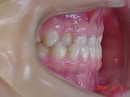

今回の症例写真は不正咬合の代表、 受け口<反対咬合> の改善症例です。

受け口 矯正前 矯正1年後

期間は1年6カ月で治療方法は独自の方法です。